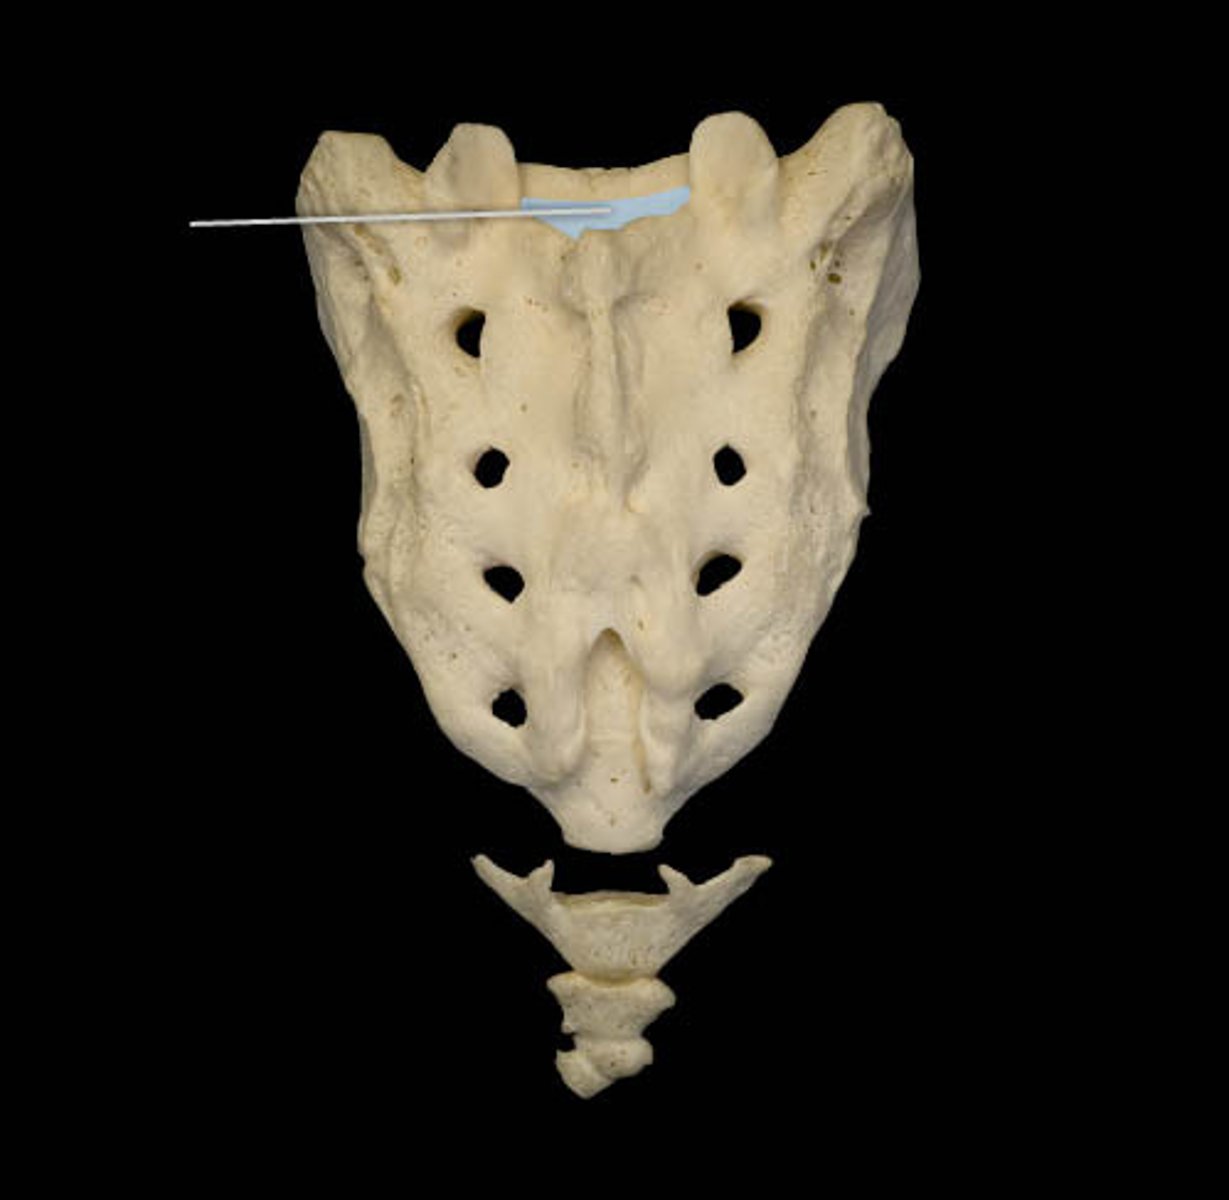

S1-S5

how many sacral vertebra are fused together

1-3

how many coccyx vertebra are fused together

S2, dural/thecal sac

the cerebral spinal fluid travels all the way down to the

sacral canal

nerves coming from cauda equina, extension of vertebral formamen

what runs thru the sacral canal

dural/thecal sac

what area is considered the end/termination of the spinal canal

S2

what level of vertebra is the dural/thecal sac located

S2 the dural/thecal sac

until what point does the subarchnoid space(where spinal fluid exists) flow down to